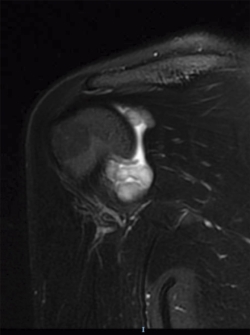

Se realizaron radiografías anteroposterior y axial de hombro, objetivándose calcificaciones intraarticulares, redondeadas, bien delimitadas. Ante dichos hallazgos, se procedió a la realización de una resonancia magnética (RM). En dicha prueba se objetivaron lesiones quísticas múltiples, bien delimitadas, algunas de ellas isointensas en T1, junto a otras lesiones hipointensas en T1 y T2 en la articulación glenohumeral compatibles con el diagnóstico de condromatosis sinovial (Figuras 1 y 2).

Figura 1. Resonancia magnética, T1 corte axial: condromatosis sinovial.

Figura 2. Resonancia magnética, T2 corte coronal: condromatosis sinovial.